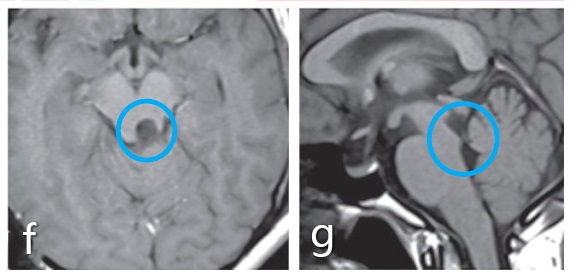

手术入路和体位:c图表示半坐位进行了手术,通过左侧小脑上天幕下入路全切肿瘤。d图显示整个外侧枕骨区域暴露在下,直到滑车神经出口(箭头所示)。e图表示脑干的进入点选择在上丘脑的侧面,然后的肿瘤切除腔约6mm

术后:f、g图术后MRI影像显示肿瘤得到了全切。患者无并发症,无其他神经系统缺陷。术后病情平稳,术后5年内无肿瘤复发。